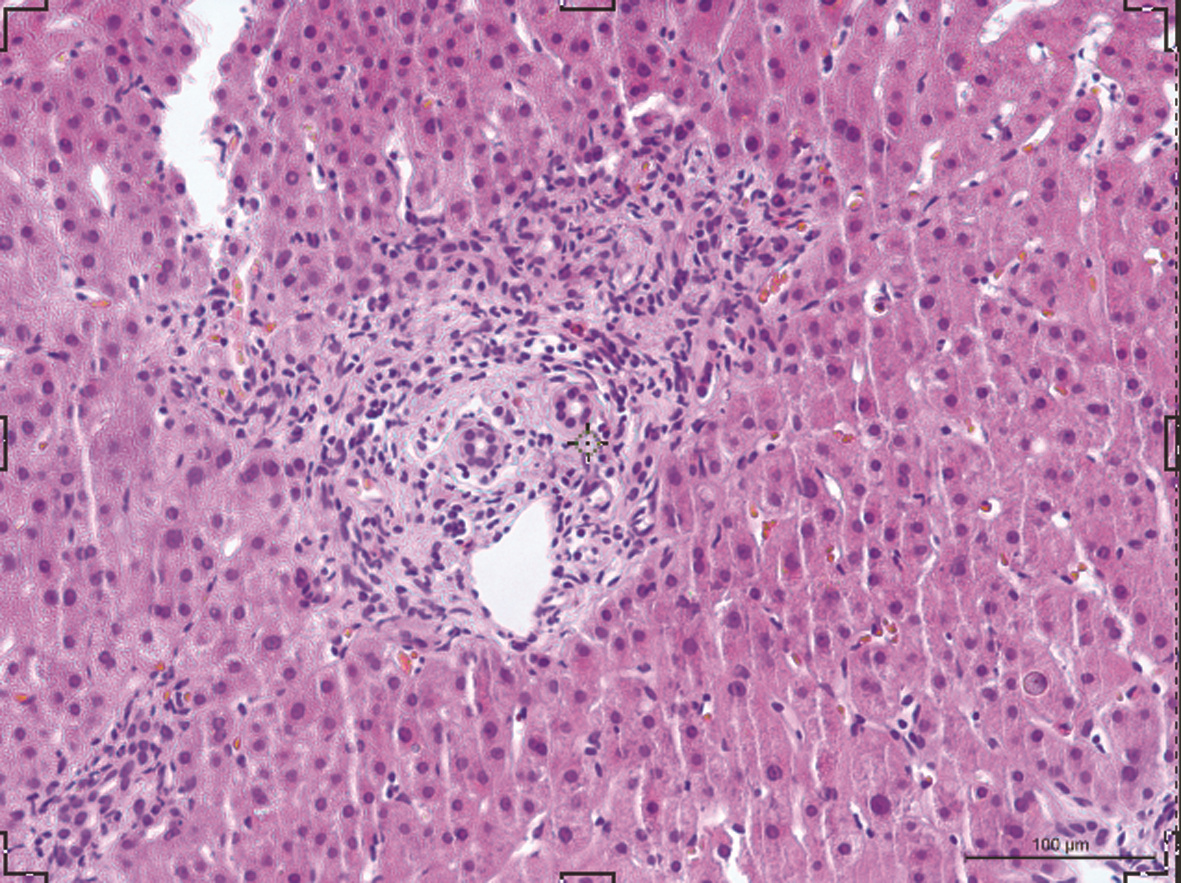

中性粒细胞胞外诱捕网在原发性胆汁性胆管炎患者中的作用初步探析

偶绎颜, 崔娜娜, 李瑶, 钱其炜, 马雄, 尤征瑞, 连敏, 王绮夏

2022, 38(4): 810-814. DOI: 10.3969/j.issn.1001-5256.2022.04.014

摘要(1558) HTML (468) PDF (3548KB)(116)

摘要:

目的  探索原发性胆汁性胆管炎(PBC)患者外周血和肝组织内中性粒细胞胞外诱捕网(NET)表达水平,及其与临床生化指标的相关性。  方法  选取2016年8月—2020年8月上海交通大学医学院附属仁济医院收治的PBC患者24例、年龄匹配的原发性硬化性胆管炎(PSC)8例以及自身免疫性肝炎(AIH)患者19例、健康对照(HC)18例,分别检测血清中髓过氧化物酶(MPO)水平,并与临床指标进行相关性分析。利用组织免疫荧光检测PBC患者肝内NET表达情况。体外实验比较PBC患者和健康对照组外周血中性粒细胞产生NET能力的差异。满足正态分布的计量资料2组间比较采用独立样本t检验,非正态分布计量资料多组间比较采用Kruskal-Wallis H检验,2组间比较采用Mann-Whitney U检验。对MPO水平与肝脏相关实验室指标进行相关性分析,计算Spearman相关系数。  结果  PBC组血清中的MPO水平[811.21(450.67~1 216.20)ng/mL]较AIH组[468.58(142.63~812.43)ng/mL]和HC组[357.54(203.52~811.21)ng/mL] 明显升高(P值均<0.05);提示在PBC患者外周血中NET的产生量显著增加。PSC患者血清中MPO水平[763.56(489.59~1 633.14)ng/mL]也较HC组显著升高(P<0.05)。MPO水平与ALP(r=0.500,P<0.05)、GGT(r=0.426,P<0.05)、ALT(r=0.521,P<0.01)和AST(r=0.547,P<0.01)水平之间存在正相关关系。免疫荧光共聚焦显示PBC患者肝内存在H3Cit、MPO共定位。体外实验观察到PBC患者外周血中性粒细胞较健康对照在体外刺激时产生NET增多,且自发产生NET亦增高。  结论  PBC患者外周血及肝内NET增多,且外周血NET的含量与肝功能生化指标呈正相关。NET或可成为评估疾病严重程度的新型生物学标志物。